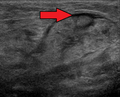

Submandibular gland inflammation as seen on ultrasound